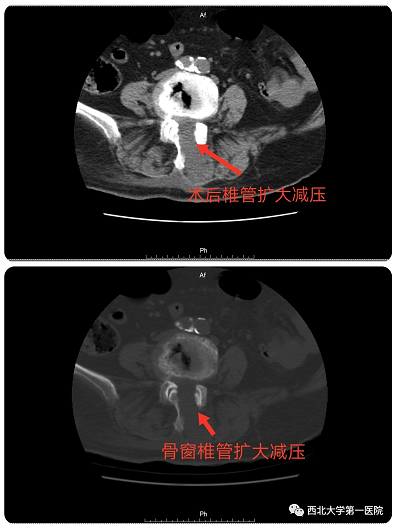

术中可见椎管减压彻底,神经根完全松解

术后复查CT可见椎管彻底减压